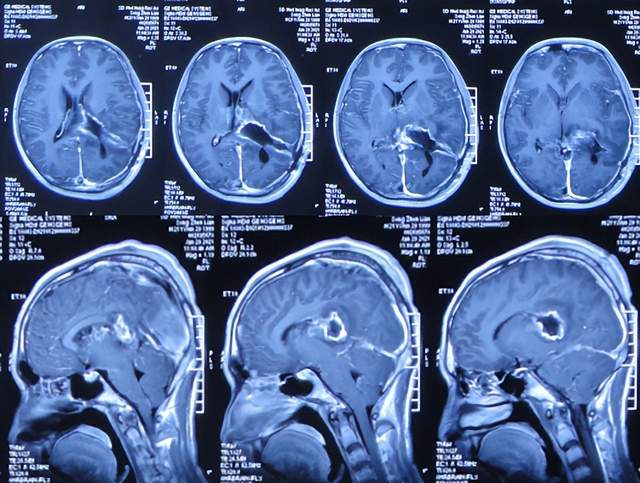

直到2021年1月8日(间断头痛4年后),因无法忍受头痛,就诊于山东省济南市商河某医院,查头颅核磁示颅内占位(图-1)。

图-1:2021年1月8日头颅核磁

为治疗脑瘤,于5天后即2021年1月13日,就诊于山东省某省级三甲医院,查头颅核磁增强(图-2)和头颅血管造影(图-3)示颅内占位。

图-2:2021年1月13日头颅核磁增强

图-3:2021年1月13日头颅血管造影

入院后5天即2021年1月18日,查头颅CT增强示颅内占位(图-4)。

图-4:2021年1月18日头颅CT增强